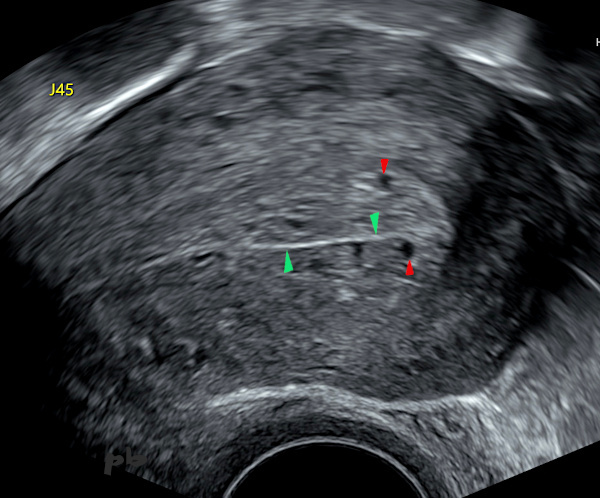

4 – Hypertrophie et glandes endométriales

Coupe sagittale par voie endovaginale. J45 du cycle.

– Endomètre épaissi.

– Echostructure homogène avec plusieurs petites images kystiques intra-endométriales (glandes ►).

– Epaisseur régulière de chaque feuillet endométrial : la ligne dite de vacuité, hyperéchogène (►), permet de bien localiser la cavité utérine.

-L’interface avec le myomètre est nette et régulière.

Simple hypertrophie avec glandes endométriales assez grosses pour devenir visibles en échographie du fait de la prolongation du cycle comme on le voit dans les grossesses débutantes.

Attention à ne pas confondre avec un sac gestationnel dans un contexte de suspicion de GEU (voir chapitre GEU image 9).

4 – Endometrial Hypertrophy and Glands

Sagittal section via endovaginal ultrasound. Day 45 of the cycle.

– Thickened endometrium.

– Homogeneous echotexture with several small intra-endometrial cystic images (glands ►).

– Regular thickness of each endometrial layer: the so-called « vacuity line, » which is hyperechoic (►), helps clearly locate the uterine cavity.

– The interface with the myometrium is sharp and regular.

This is a simple hypertrophy with endometrial glands large enough to be visible on ultrasound due to cycle prolongation, as seen in early pregnancy.

Caution: Do not confuse this with a gestational sac in cases of suspected ectopic pregnancy (see Ectopic Pregnancy chapter, image 9).